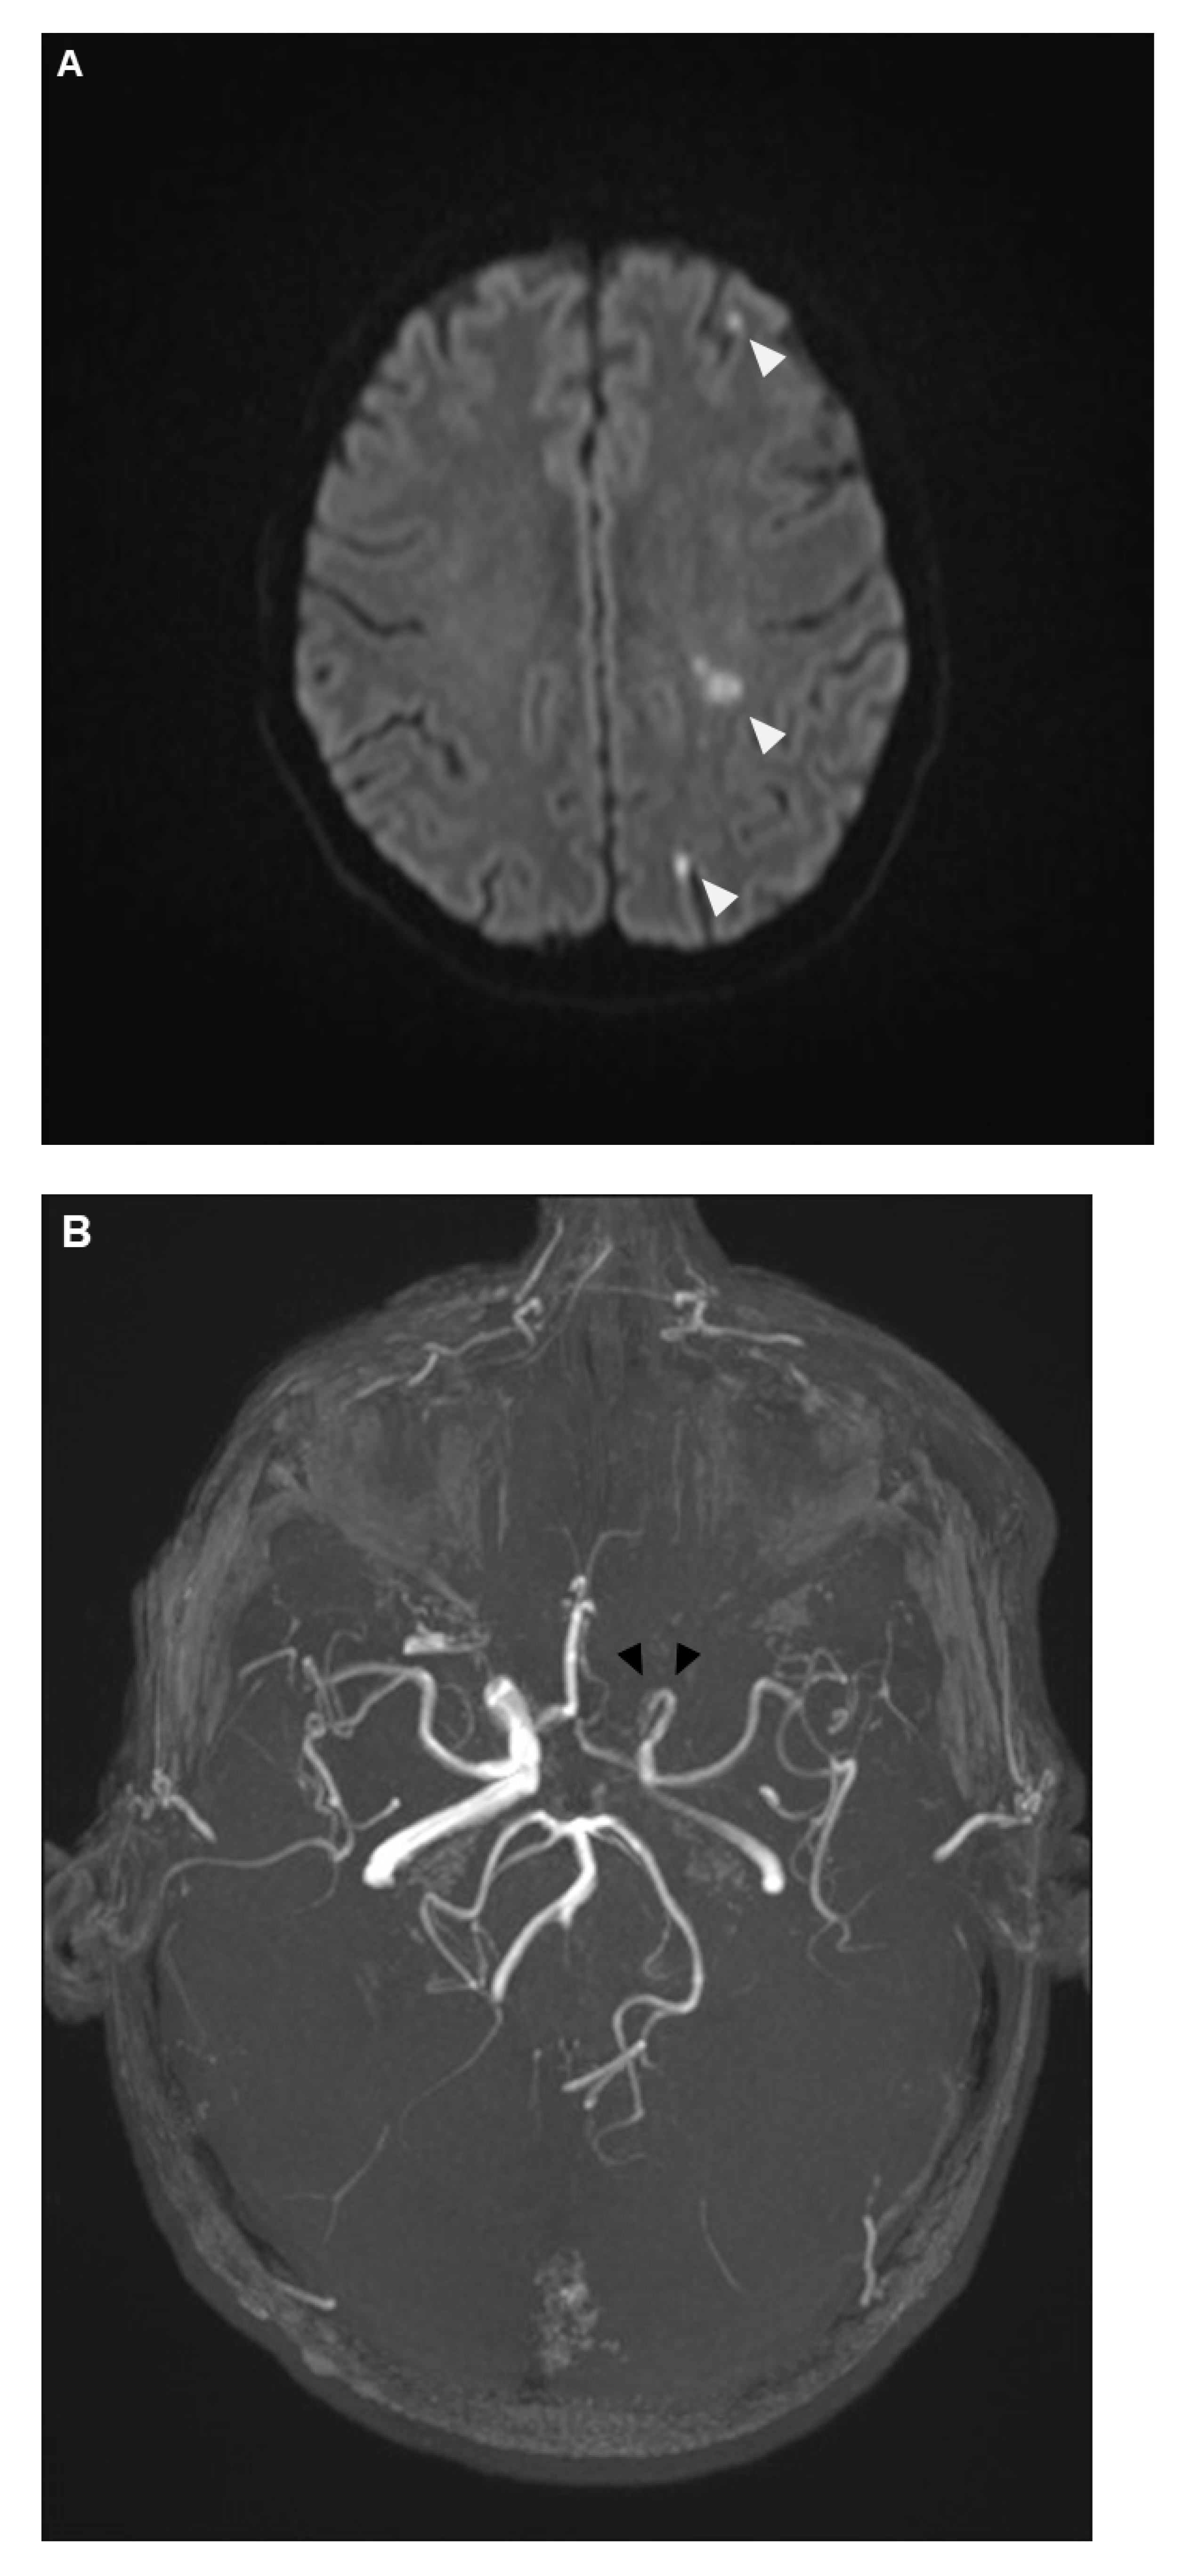

The patients experienced further clinical deterioration marked by decreased vigilance, worsening aphasia, and intensified right-sided hemiparesis, resulting in an NIHSS of 15 points. On day 7 after initial presentation at the first hospital (day 11 after symptom onset), the patient was transferred to our university clinic and admitted to our neurological intensive care unit (NICU). MRI was repeated, showing unchanged local inflammatory changes; however, new vessel abnormalities as well as diffusion restriction in the left middle cerebral artery territory were observed (Figure 5A,B). Based on these findings and the differential diagnosis of vasculitis or vasospasm, a digital subtraction angiography (DSA) was performed (Figure 5C).

Figure 5.

Diffusion-weighted imaging in cerebral MRI showed now new areas of ischemia within the middle cerebral artery territory (A). Further evaluation with cerebral MR Angiography (B) revealed new, compared to earlier imaging a few days before, irregularities in the vessel walls of the left intracranial internal carotid artery, with moderate-to-severe luminal narrowing. To clarify these findings, Digital Subtraction Angiography (DSA) was performed (C). The DSA indicated that while the extracranial segment of the left internal carotid artery appeared normal, significant irregularities were present beginning at the petrous segment. These irregularities (black arrows) caused moderate luminal narrowing with partial filling of the middle cerebral artery from crossflow via the A1 segment. During the venous phase, adequate contrast filling of the cavernous sinus was observed, effectively ruling out a cavernous sinus thrombosis. Despite local administration of 3 mg Nimodipine over 30 min, there was no alteration in the observed vascular irregularities, supporting the conclusion that these changes were inflammatory rather than spasmodic.